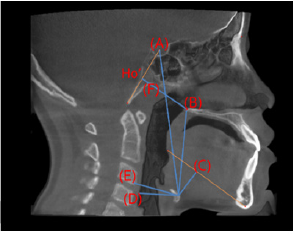

As mentioned above, the effect of RAMPA on maxillae is the anterosuperior protraction leading to the forward rotation of maxillary bone and mandibular bone, which results in more spacious upper airway and affecting the position of hyoid bone. In order to see the effects on various phenomena including volume of the upper airway and the position change of hyoid bone. (Figure 6) shows the planes defining the upper airway. Total upper airway volumes are composed of retropalatal volumes and retroglossal volumes as shown in (Figures 7 & 8). Shows how to define the position of hyoid bone and measure the change of the position. After RAMPA treatments, there were significant increase of retroglossal and total airway volume (P<0.05) as listed in (Table 3). In addition, the horiz.dH and C3-H, which indicate the anterior position of the hyoid bone, increased and HyS and vert.dH, which represent the vertical facial dimension, decreased after treatment. However, in the case of the position change of hyoid bone, little effect was shown because of short period (avg. less than 6 mos.) of RAMPA therapy because more than a year or two would be needed for shifting the positon of hyoid bone.

Figure 8:The measurement defining the position of hyoid bone;

a. HyS: linear vertical distance from Hy (uppermost point of the hyoid) to S;

b. vertical dH: linear vertical distance from H (most anterior point of the hyoid) to the PNS;

c. HyMP: vertical distance from Hy to the mandibular plane; vv

d. horiz.dH: linear horizontal distance from H to the posterior wall of the hypopharynx,

e. C3-H: linear measure from the H to the most anterior and inferior point of C3;

f. Ho’-PNS: linear measure from Ho' to PNS; Ho': Intersection of S-Ba with a line perpendicular to S-Ba registered on PNS.